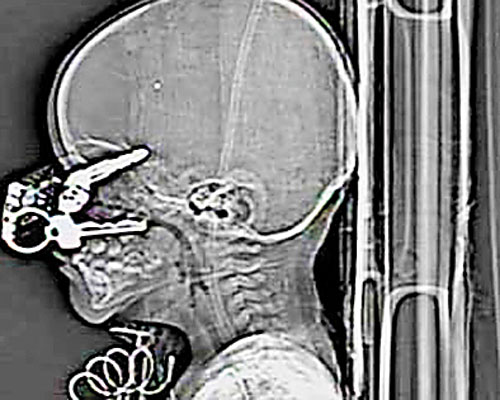

Un băieţel de un an din Missouri, SUA, a scăpat fără nici un fel de sechele, după ce o cheie de maşină i-a intrat prin pleoapă până în creier. Nicholas Holderman se juca prin casă zilele trecute, când a căzut cu faţa peste cheile de la maşina tatălui său, care i-au penetrat pleoapa ochiului stâng şi i-au ajuns până în creier. Îngroziţi, părinţii micuţului l-au dus la spital, unde medicii au reuşit să extragă obiectul străin din capul micuţului.